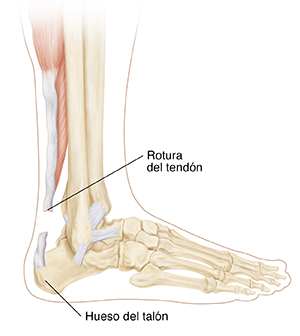

Rotura del tendón de Aquiles

El tendón de Aquiles es una extensa franja de tejido en la parte posterior del tobillo. Conecta los músculos de la pantorrilla con el hueso del talón. El tendón le ayuda a dirigir el pie hacia abajo, a levantarse de puntillas y a empujar cuando camina. Se utiliza prácticamente cada vez que se mueve la pierna. No obstante, el esfuerzo repetido puede hacer que el tendón sea más propenso a lesionarse. Puede inflamarse y desarrollar pequeños desgarros (tendinitis). Un desgarro completo del tendón se conoce como rotura del tendón de Aquiles.